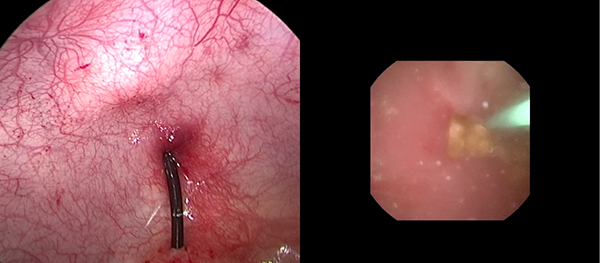

一名14岁男性青少年因活动后血尿检查发现右肾积水并右肾结石,进一步检查发现患儿右肾积水的原因是肾盂输尿管连接部梗阻所致。由于患儿肾盂输尿管连接部狭窄,常规输尿管软镜碎石无法实施。由于结石位于右肾下盏,盏颈狭窄、腹腔镜下无法直接取石。经小儿泌尿外科讨论后,决定在患儿行腹腔镜肾盂成形术的同时联合输尿管软镜进行右肾下盏激光碎石。手术在吴荣德教授指导下,由刘伟主任医师、杜国强副主任医师等共同完成。经腹腔镜探查发现患儿肾盂输尿管连接部狭窄,狭窄段长0.5cm,肾盂扩张积水。于肾盂切开约0.5cm,自腹壁置入输尿管软镜经肾盂切口进入,在下盏内见一大小约1.0×0.8cm黄褐色桑葚样结石,经输尿管软镜置入钬激光光纤予以碎石。碎石后取出大块结石颗粒,吸净碎屑后行腹腔镜下右肾盂成形术。患儿术后恢复良好,顺利出院。后期患儿规律复查,未再出现血尿、腹痛等不适症状。

一名8岁女性儿童因血尿检查发现左肾输尿管积水并左输尿管末端结石入院治疗,检查发现患儿为输尿管末端狭窄合并左肾结石。由于患儿输尿管末端狭窄可经气膀胱腹腔镜手术,无法处理左肾结石,并且输尿管末端狭窄无法行输尿管软镜手术。经全科讨论后,决定在患儿行气膀胱腹腔镜输尿管再植的同时联合输尿管软镜进行左肾激光碎石。手术在吴荣德教授指导下,由刘伟主任医师、杜国强副主任医师等共同完成。气膀胱腹腔镜下切除左侧输尿管末端狭窄,经尿道置入输尿管软镜经输尿管末端进入,在下盏内见一大小约0.8×0.7cm黄褐色扁圆形结石,经输尿管软镜置入钬激光光纤予以碎石。碎石后行左侧输尿管膀胱再植术(Leadbetter术式)。患儿术后恢复良好,顺利出院。后期患儿规律复查,未再出现血尿、腹痛等不适症状。